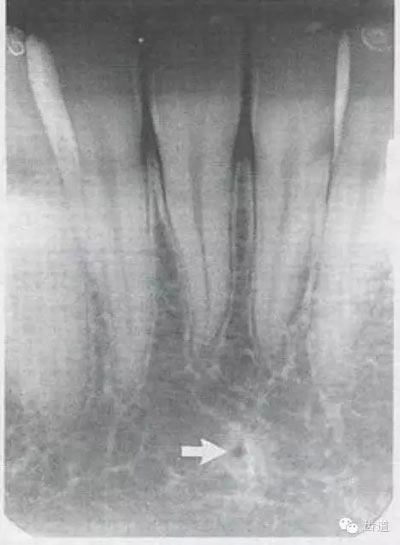

牙頸部Burnout征象:有時因投照技術(shù)問題而造成牙頸部近中或遠(yuǎn)中呈低密度影像,位于牙釉質(zhì)和牙槽嵴頂之間。

在兩個中切牙牙根之間或稍上方,多呈橢圓形密度低的影像,切牙孔影像可重疊在一側(cè)中切牙牙根尖處,易誤認(rèn)為根尖周病變,可視牙周膜和骨硬板是否完整加以鑒別

位于兩側(cè)中切牙牙根之間,由牙槽突向上,呈直線狀密度低的影像。其兩側(cè)為密度高的影像,為兩側(cè)上頜骨腭突的致密骨層。

鼻腔位于上切牙根尖的上方,顯示為對稱性半圓形密度低的影像,其中間被一密度高的骨隔分開為鼻中隔